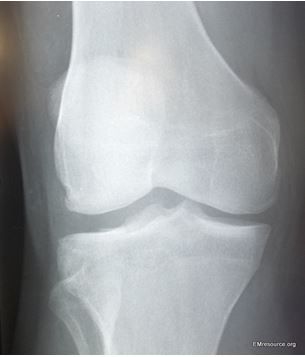

You let your judgment trump the imaging criteria and order a knee x-ray film; results are shown at right (Figure 1).

Answer: Occult tibial plateau fracture

The x-ray film demonstrates a fat-fluid level. Even if no fracture is actually seen, a fat-fluid level means an occult fracture is present-a finding similar to the fat-pad sign after an elbow injury. In the knee, the occult fracture is most often a nondisplaced lateral tibial plateau fracture. The mechanism for this injury (rotating the upper body with all weight on one leg) is very unusual because it is usually the result of substantial force, such as being struck by a car or a fall from a height. Ligamentous injury complicates this fracture in about 25% of cases.

Management is usually nonoperative for nondisplaced or minimally displaced fractures, but surgery is required to align the joint surface when there is significant displacement. No fracture was seen on any views of our dancing patient, but Figure 2 is an x-ray film of a basketball player’s knee after it had been hyperextended and also shows a fat-fluid level on the lateral view. The AP view (not shown) revealed a subtle lateral plateau fracture.